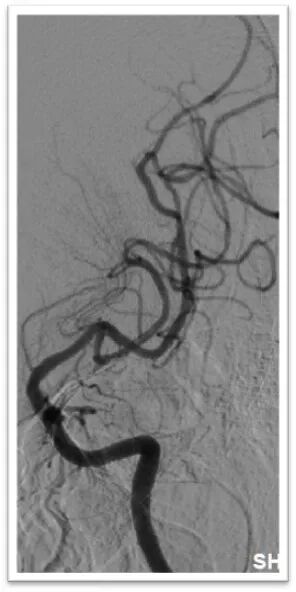

图4:DSA提示主动脉弓为牛角弓,左侧颈总动脉发自头臂干动脉,右侧颈内动脉造影提示前交通动脉开放,呈双干大脑前动脉,左侧大脑前动脉通过软膜支向左侧大脑中动脉供血区域代偿,双侧椎动脉均势供血,左侧大脑后动脉通过软膜支向前代偿供血;左侧颈总动脉闭塞,残端呈杯口状,近端可见白色血栓影,初步考虑栓塞性闭塞。